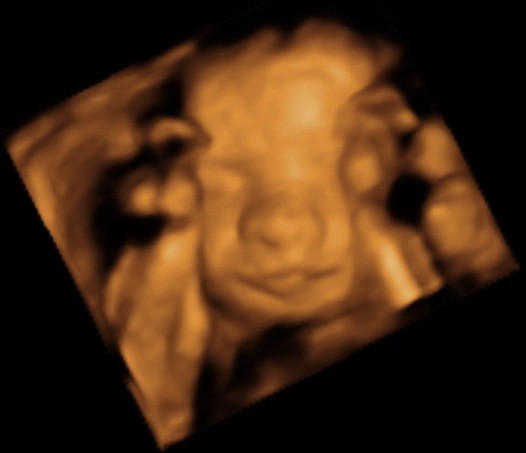

ślicznyNie wiem, ktory temat odpowiedni, wiec wstawie fotki naszego synka tutaj (nie sa to medyczne skany, wiec watek lekarski chyba nie pasuje, nie sa to tez zdjecia brzuszka...)

Zobacz załącznik 435455

Zobacz załącznik 435456

Zobacz załącznik 435457

Zobacz załącznik 435458

Zobacz załącznik 435459